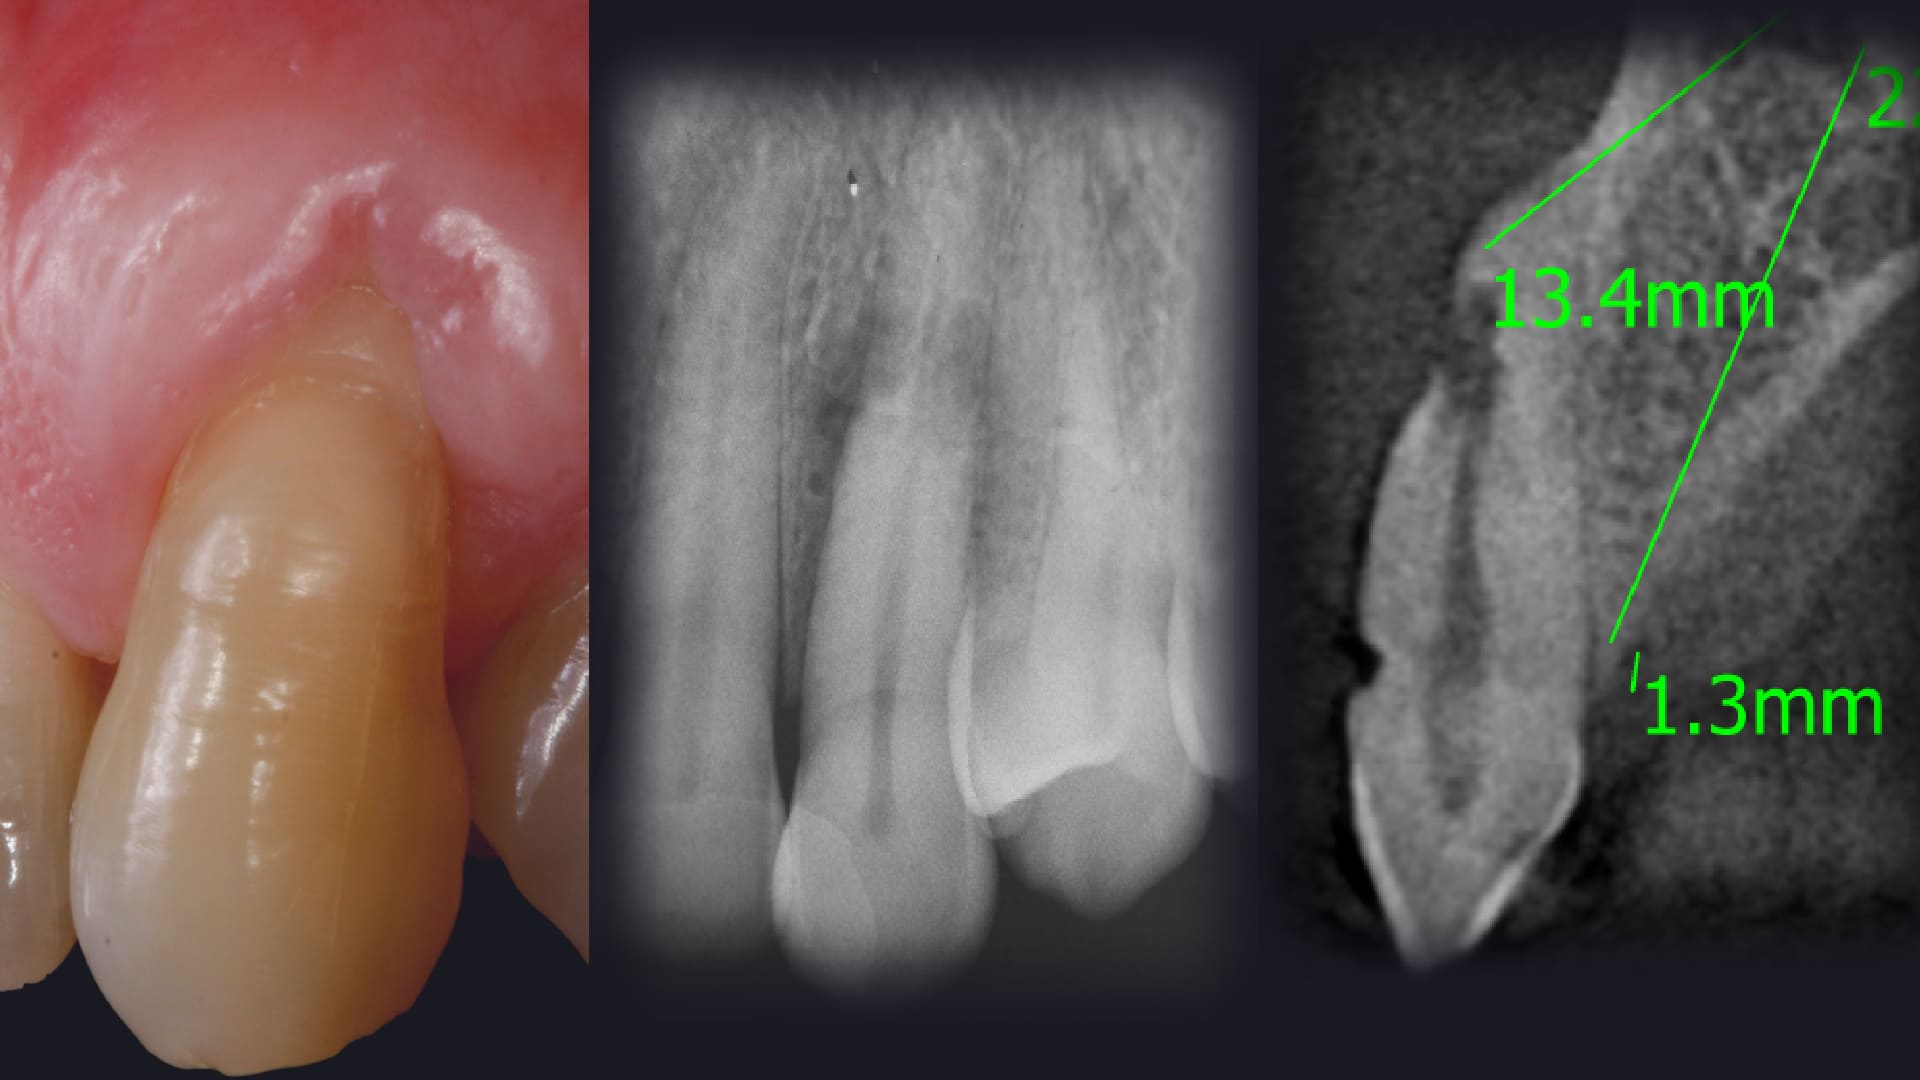

Master diagnostic protocols, classifications and ImpalntePerio Decision trees.

IP Protocols and Decision Tree at Fresh Sockets.

Minimally Invasive Tooth Extraction.

Biology of The socket healing.

Biomaterial Selection To Fill The Gap.

When, Why, and How to use the Connective Tissue Graft at.

Immediate Implants.

The importance of the Immediate Provisional Restorations.